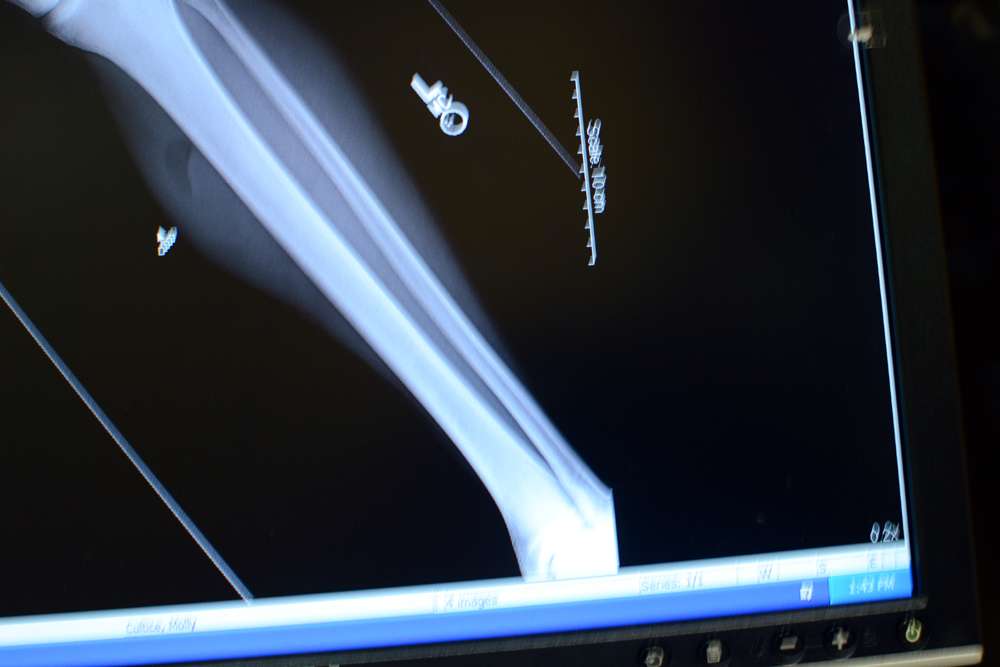

Here are pictures of Matt’s gross leg.